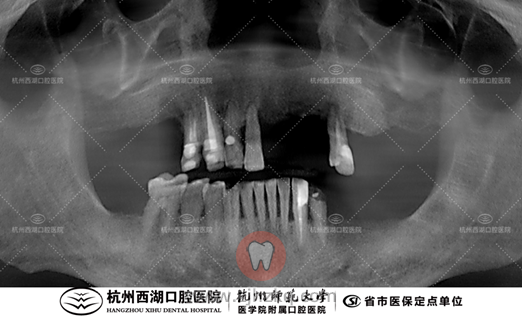

术前CBCT照如下